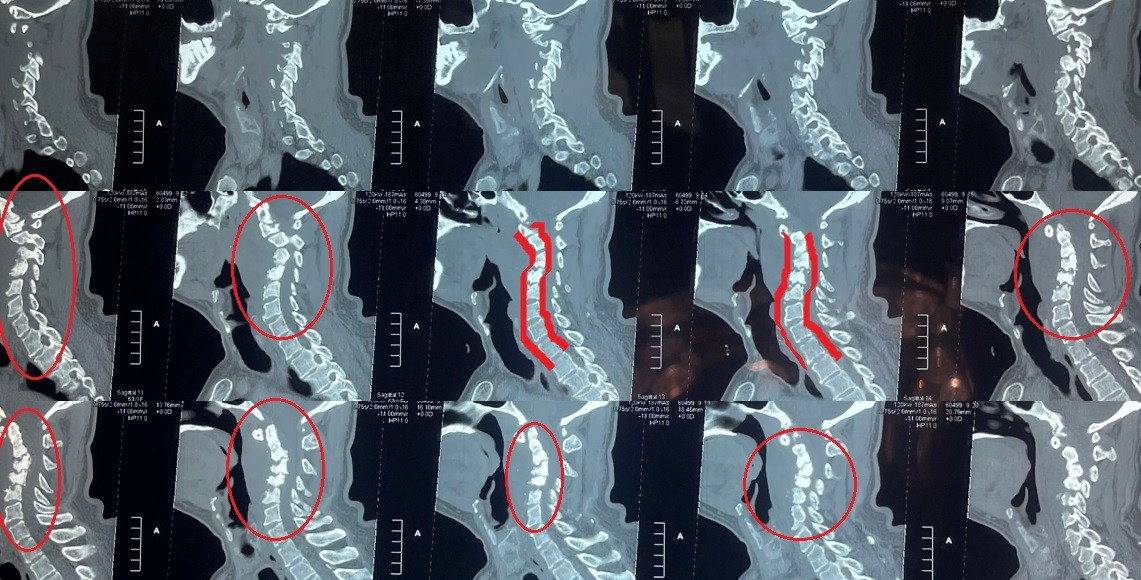

cervical vertebrae kyphosis repair